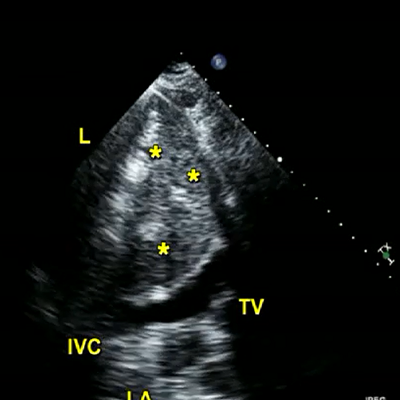

Echo: apical four chamber view.

1 MB